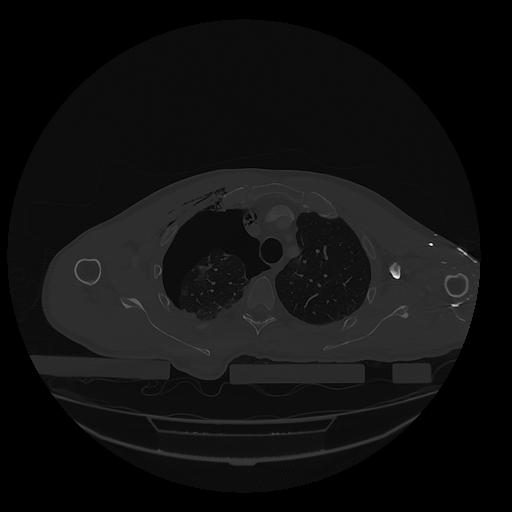

31 PULMON,CE,Vol,1.0,PULMON,,